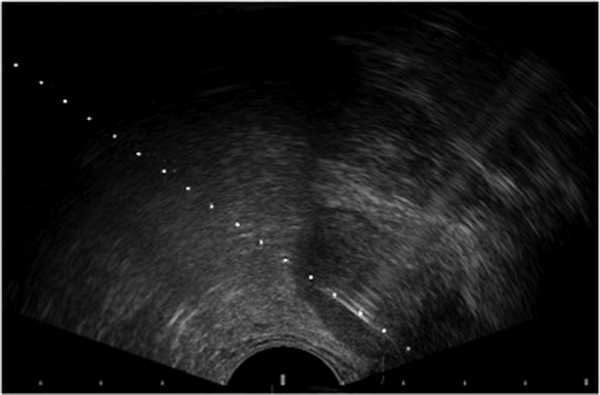

Пациент А., 32 лет, обратился в клинику урологии МГМСУ с жалобами на гипертермию до 37,0-37,3 °С в вечернее время в течение 4 мес до настоящей госпитализации, затрудненное мочеиспускание вялой струей, боли в области промежности, эпизоды острой задержки мочи, самопроизвольно разрешавшиеся. Пациент холост, детей не имеет. Из анамнеза известно, что в 16-летнем возрасте при амбулаторном ультразвуковом исследовании (УЗИ) была выявлена единственная левая почка. В последующем в другом лечебно-профилактическом учреждении при УЗИ выявлено образование мочевого пузыря (рис. 1). Рисунок 1. Трансабдоминальное УЗИ пациента А.